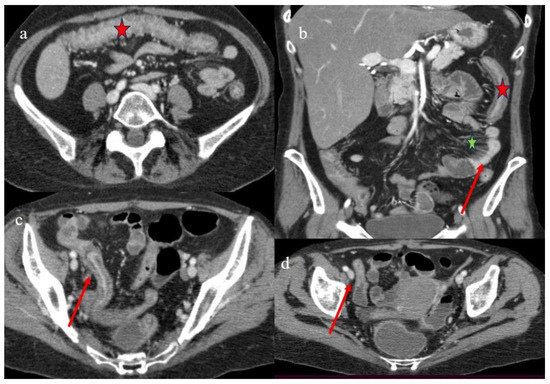

| 5 | 47 | F | ALL PH+ | BM | MUD 10/10 | 9 months | 9 months | AP + SBO | co | III | D |

| 5 | P | P | Multisegmental thickness with stenosis on jejunal loops and SBO and segmental and focal thickness on the terminal ileus and appendix | Diffuse parietal thickness with stratified enhancement | Mild comb sign, poor reactive mesenteric lymph node, small air bubbles in the ascites | Small splenic areas of ischemia |